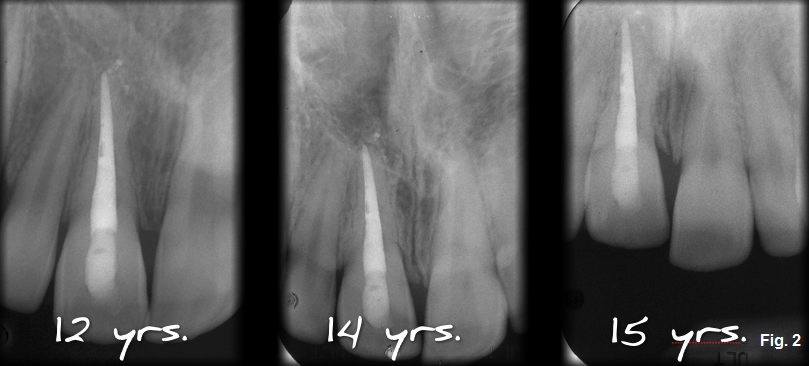

- How fast is the resorption occurring? As can be seen from the radiographs the patient brought (Fig. 2), the rate of resorption seems to be progressing very slowly.